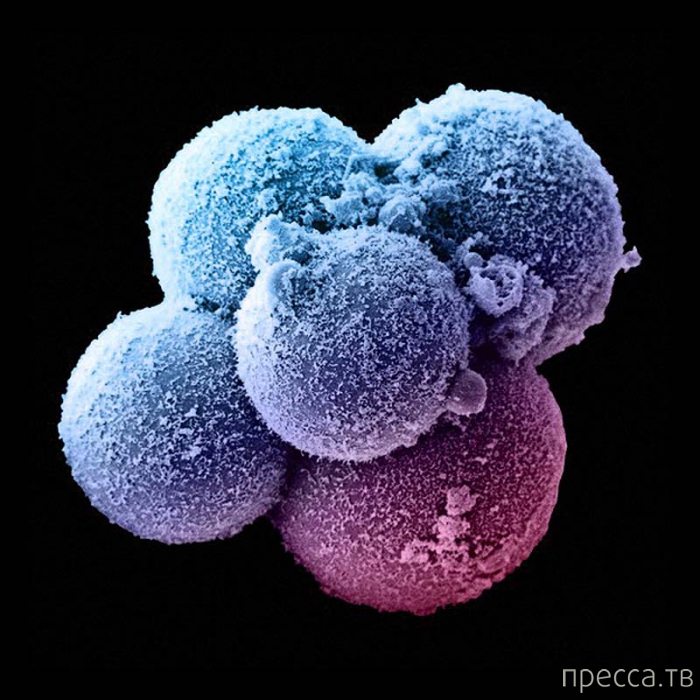

1. Через 4 дня после оплодотворения.

После оплодотворения зигота уже обладает предопределенным полом (вот эта, например, девочка!) и уникальным набором ДНК. Ее ДНК будет определять развитие ее тела в течение следующих девяти месяцев (а потом и всю жизнь).

1. Через 4 дня после оплодотворения.

После оплодотворения зигота уже обладает предопределенным полом (вот эта, например, девочка!) и уникальным набором ДНК. Ее ДНК будет определять развитие ее тела в течение следующих девяти месяцев (а потом и всю жизнь).